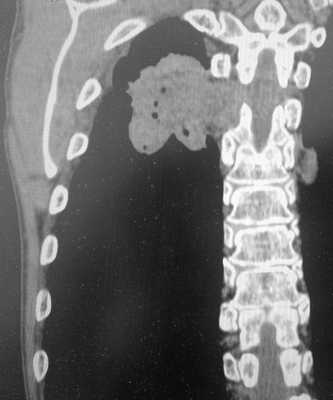

Пример рака легких 4 стадии. Не показано оперативное лечение, только химиотерапия. Имеет место прорастание в ребра и позвоночник, а также в мягкие ткани грудной стенки. В строме опухоли видны множественные гиподенсные (темные) участки, содержащие газ - зоны распада.